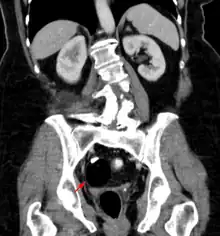

CT showing a teratoma of the ovary: fatty formation with a smooth boundary, with a dense part, possibly a tooth.